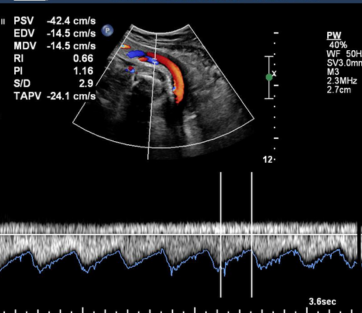

Multivessel Doppler

Multivessel Doppler is a medical imaging technique that uses Doppler ultrasound technology to assess blood flow in multiple blood vessels within the body. It helps healthcare providers decisions patient care

- Ultrasound Probe

- Color Doppler

- Spectral Doppler

- Obstetrics